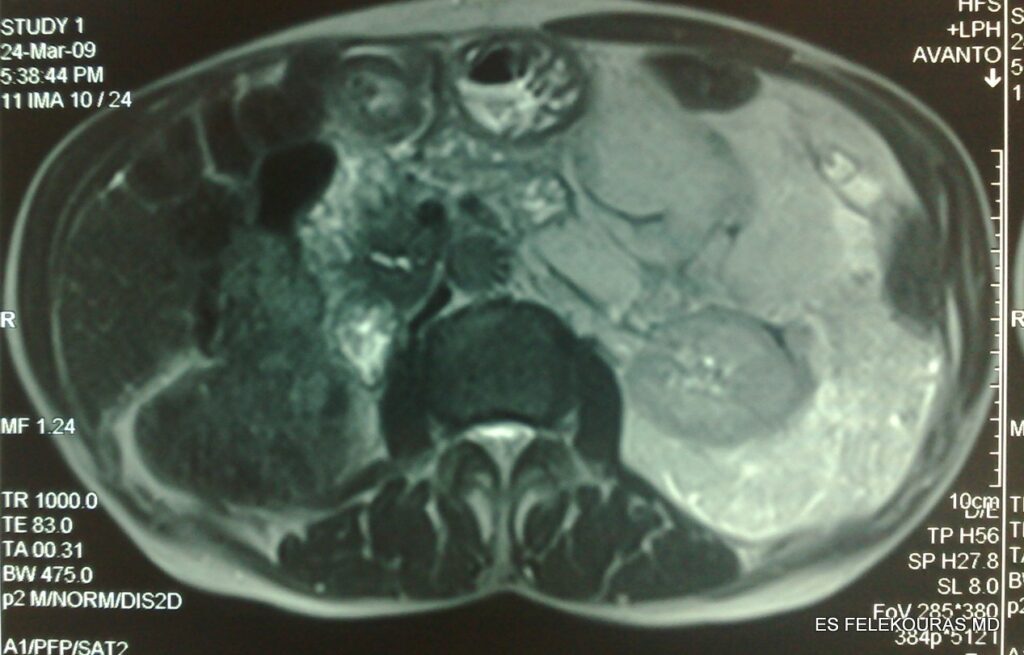

Η διάγνωση θα πρέπει να βασιστεί στην ΑΤ και λιγότερο στην MRI με τις αρχές που έχουμε ήδη περιγράψει εδώ, μια και η κλινική εξέταση δεν είναι ιδιαίτερα διαφωτιστική εκτός από την ψηλάφηση του όγκου. Η Μαγνητική Τομογραφία (MRI) είναι ένα θαυμάσιο συμπλήρωμα για την αξιολόγηση των όγκων στην πύελο. Η μαγνητική Τομογραφία της πυέλου μπορεί να βοηθήσει σημαντικά στον καθορισμό της έκτασης της νόσου και τα ποιοτικά χαρακτηριστικά της.